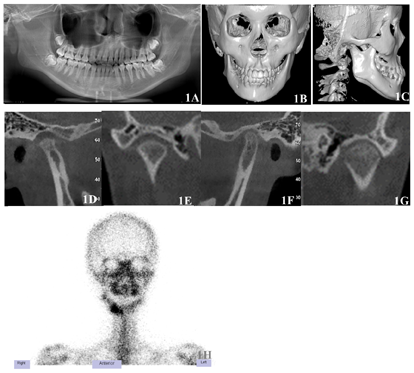

(1)关节术前X线检查:曲面断层X线片显示左侧下颌较右侧在三维方向上增大,左侧髁突颈较右侧更为细长,左侧下颌升支较右侧长约4 mm。头颅三维重建可见颏前点相对于面中线右偏3.5 mm;双侧下颌体界限不对称。锥体束计算机断层扫描(CBCT)显示双侧颞下颌关节闭口位时,右侧关节前、后、上间隙等大,右侧髁突骨质吸收,形态短小,骨质轻度硬化;左侧关节前间隙增大,髁突头体积增大。SPECT检查结果显示左侧髁突放射性密度增高,左侧髁突同位素摄取百分率约为60.1%。综上,满足"活跃型左侧CH(垂直型)"的诊断特征[4,5](图1)。